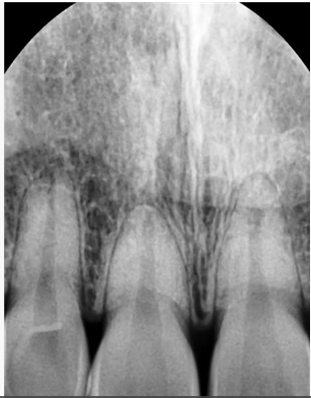

앞니 1개의 치아 뿌리가 다른 것보다 짧습니다. 이런 경우 교정을 하면서 치아에 힘을 주면 치아 뿌리가 더 짧아지는 치근흡수가

일어날 가능성이 있습니다. 그러나 꼭 교정을 하시고 싶으면 교정하는 것도 큰 무리가 아닐 수도 있습니다. 양악수술은 큰 수술이며

현재 상악 전치와 하악 전치의 뿌리의 길이가 정상적인 것보다 짧기 때문에 무리하게 후방견인을 하다가 치아 뿌리가 더 짧아지게 되면 나중에 잇몸뼈의 높이가 낮아지게 되었을 경우에 조기에 상실할수 있는 가능성이 있습니다.